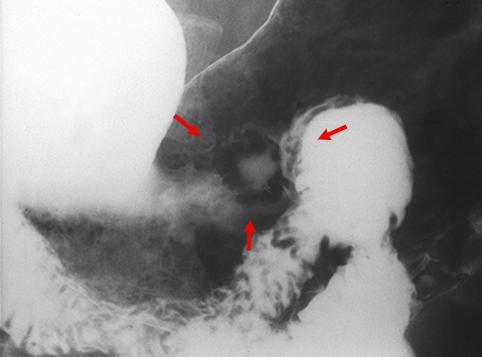

疾病(病理主体)的分类恶性上皮性肿瘤/腺癌

部位(按器官分)胃(部位)/体部

检查方法X线

肿瘤的肉眼分类0型(表在型)/IIa型(IIa+IIc)

肿瘤最大直径15~19

肿瘤的深度sm